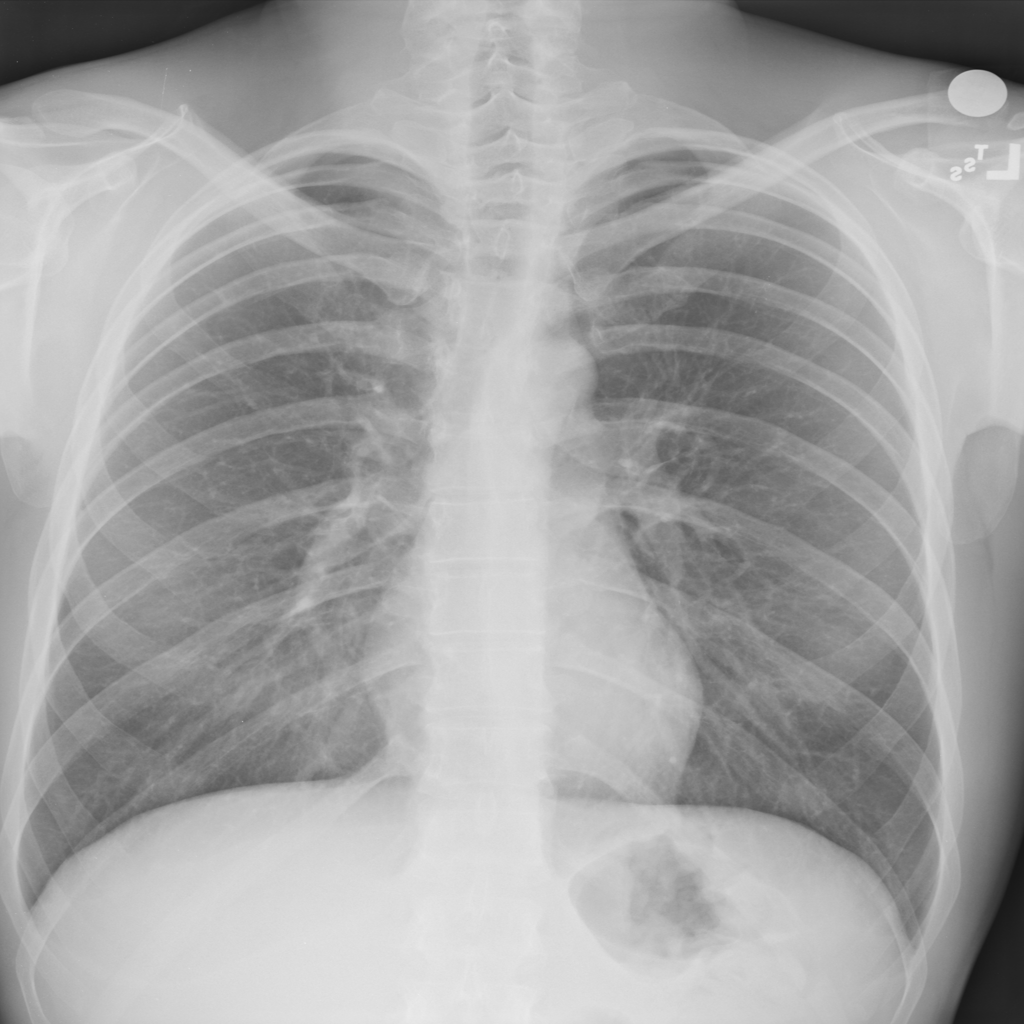

NIH Chest X-Ray dataset (Wang et al., 2017) is a large-scale medical imaging dataset comprised of 112120 X-ray images from 30805 patients. Figure 2 shows a few sample X-Ray images from the dataset. The X-ray images come labeled with up to 14 diseases and “No finding” by natural language processing (NLP) models based on the original radiological reports of each X-ray. We only select samples with “No Findings” and disease “Effusion” for the scope of our experiments. We use “Effusion” as the target label, and “Patient gender” as the sensitive attribute. After removing entries filled with N/A and abnormal values, we have a dataset with 73669 samples, and 13316 (18.1%) are labeled “Effusion”. In addition, we resized each image into size (256 * 256 * 3) with 3 channels both for computational reasons and the requirement for using pre-trained models during the training process (to be discussed in Section 6). Images are also normalized using the required mean and standard deviation based on the pre-trained model used in the experiments (Sandler et al., 2019). Detailed statistics of NIH Chest X-Ray are in Table 4.

EffusionEffusion

Total 1 0 Total

gendergender

1 7434 (10.1%) 33916 (46.0%) 41350 (56.1%56.1\%)

0 5882 (8.0%) 26437 (35.9%) 32319 (43.9%)

Total 13316 (18.1%18.1\%) 60353 (81.9%81.9\%) 73669 (100.0%)

Table 4. Statistics for NIH-Chest X-Ray dataset. EffusionEffusion is used as target label and gendergender as sensitive attribute.

Refer to caption

Figure 2. Four sample Chest X-ray images from NIH Chest X-Ray dataset.